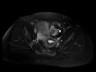

MR images demonstrate left ovarian mass containing fat and soft tissue. Left ovarian mass that contains: Fat (bright in T1 image and fat suppression in T1 fat sat and STIR images), soft tissue-dermoid plug (increased enhancement in T1+C fat sat images).

Conventional radiograph can show calcific and tooth components in the pelvis. An ovarian dermoid is seen as a unilocular cystic adnexal mass with some mural components on ultrasound. CT images demonstrate fat areas with very low Hounsfield values, fat-fluid level, calcification, Rokitansky protuberance. Pelvic MRI shows the presence of fat. Fat suppression technique is used to differentiate between ovarian dermoid cyst and hemorrhagic cyst. Dermoid cyst contains fat and its signal will be suppressed in T1 fat sat and STIR images (2, 3).